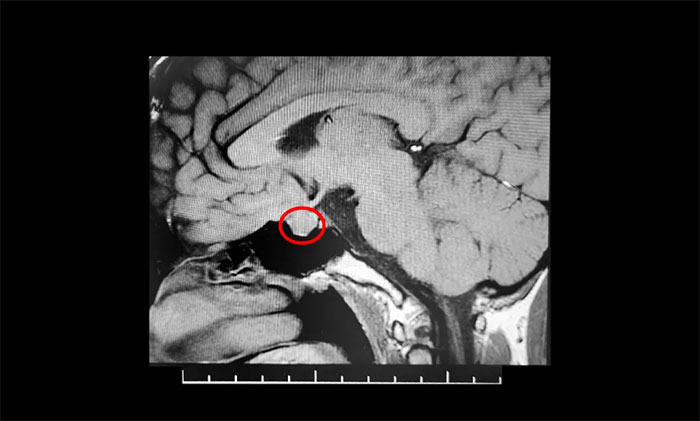

鞍区MRI平扫+增强显示:垂体前叶内见一矢横高径约1.2*1.9*1.1cm异常信号灶,边缘光整,鞍底下陷。垂体柄缩短,视交受压上抬。检查催乳素超3000μIU/mL,远超正常值。

结合患者以往影像资料和内分泌科检查结果,由潘仁龙主任、李士其教授、吴治群博士组成的专家团队会诊判断,婷婷患了泌乳素垂体瘤。

▲ 垂体大腺瘤超蝶鞍生长